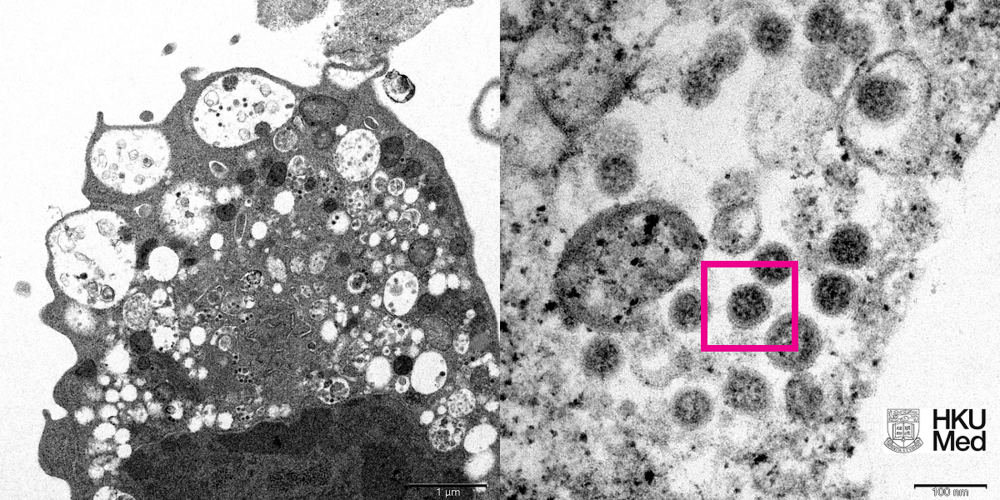

HKU's Li Ka Shing Faculty of Medicine also revealed an electron microscope image of Omicron.

The micrograph of a monkey kidney cell infected with the variant showed the damaged cell containing small black viral particles as well as the corona-shaped spikes on the virus surface.